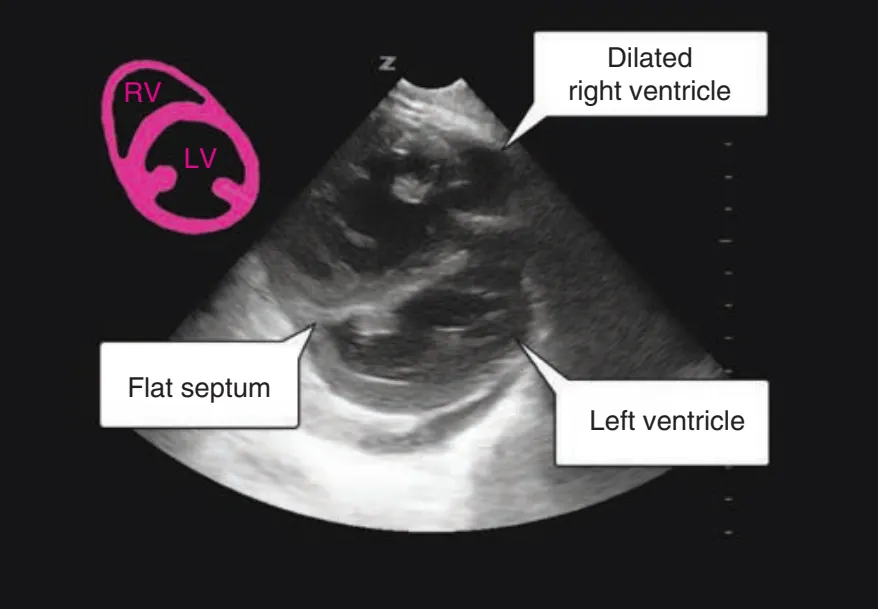

심한 경우 : Septal deviation, RV-to-left ventricle end-diastolic diameter >1 in AP4C view

IVS의 Flattening 소견 ⇒ RV pressure 증가를 의미함. 정상은 좌상단 그림처럼 보여야 함.